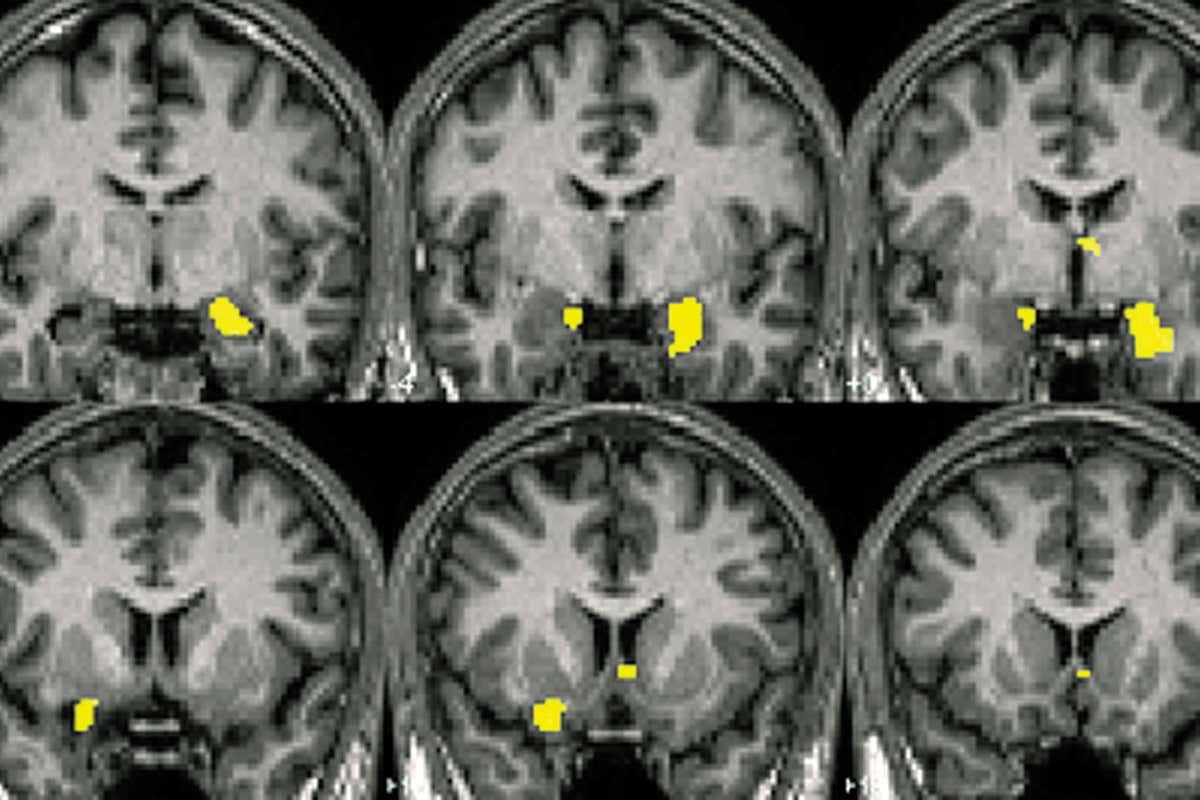

They analysed how regions of the brain’s visual cortex responded to images containing four different types of object: humans, animals, buildings and food. The data came from a volunteer who viewed more than 1200 images while an fMRI machine measured their brain response.

The different objects had their own corresponding pattern of brain activity, and the strength of the signals indicated how difficult each image was to classify.